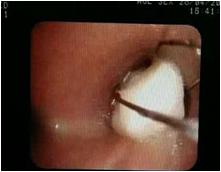

呼吸科成立以来,共开展0岁以上儿童德国耶格肺功能检查500余例;FeNO气道检查200余例,彻底解决宿迁地区儿童肺功能检查需要到外地就医的尴尬。开展雾化吸入、储雾罐、准纳器等家庭治疗,方便病人家庭治疗哮喘。2019年荣获江苏省哮喘标准化门诊称号。针对各种原因引起的慢性咳嗽,难治性肺炎,支气管异物,不明原因喘息,呼吸困难等患儿,开展气管镜检查及治疗100余例,其中最小患儿为2月龄小婴儿。联合心胸外科治愈1例右位主动脉弓合并主气管狭窄,支气管异物,肺部感染,呼吸衰竭患儿。开展气动水雾冲洗并改良技术,无伤害治疗过敏性鼻炎,鼻炎、鼻窦炎,腺样体肥大,睡眠呼吸暂停综合征等上气道慢性疾病1000余例。